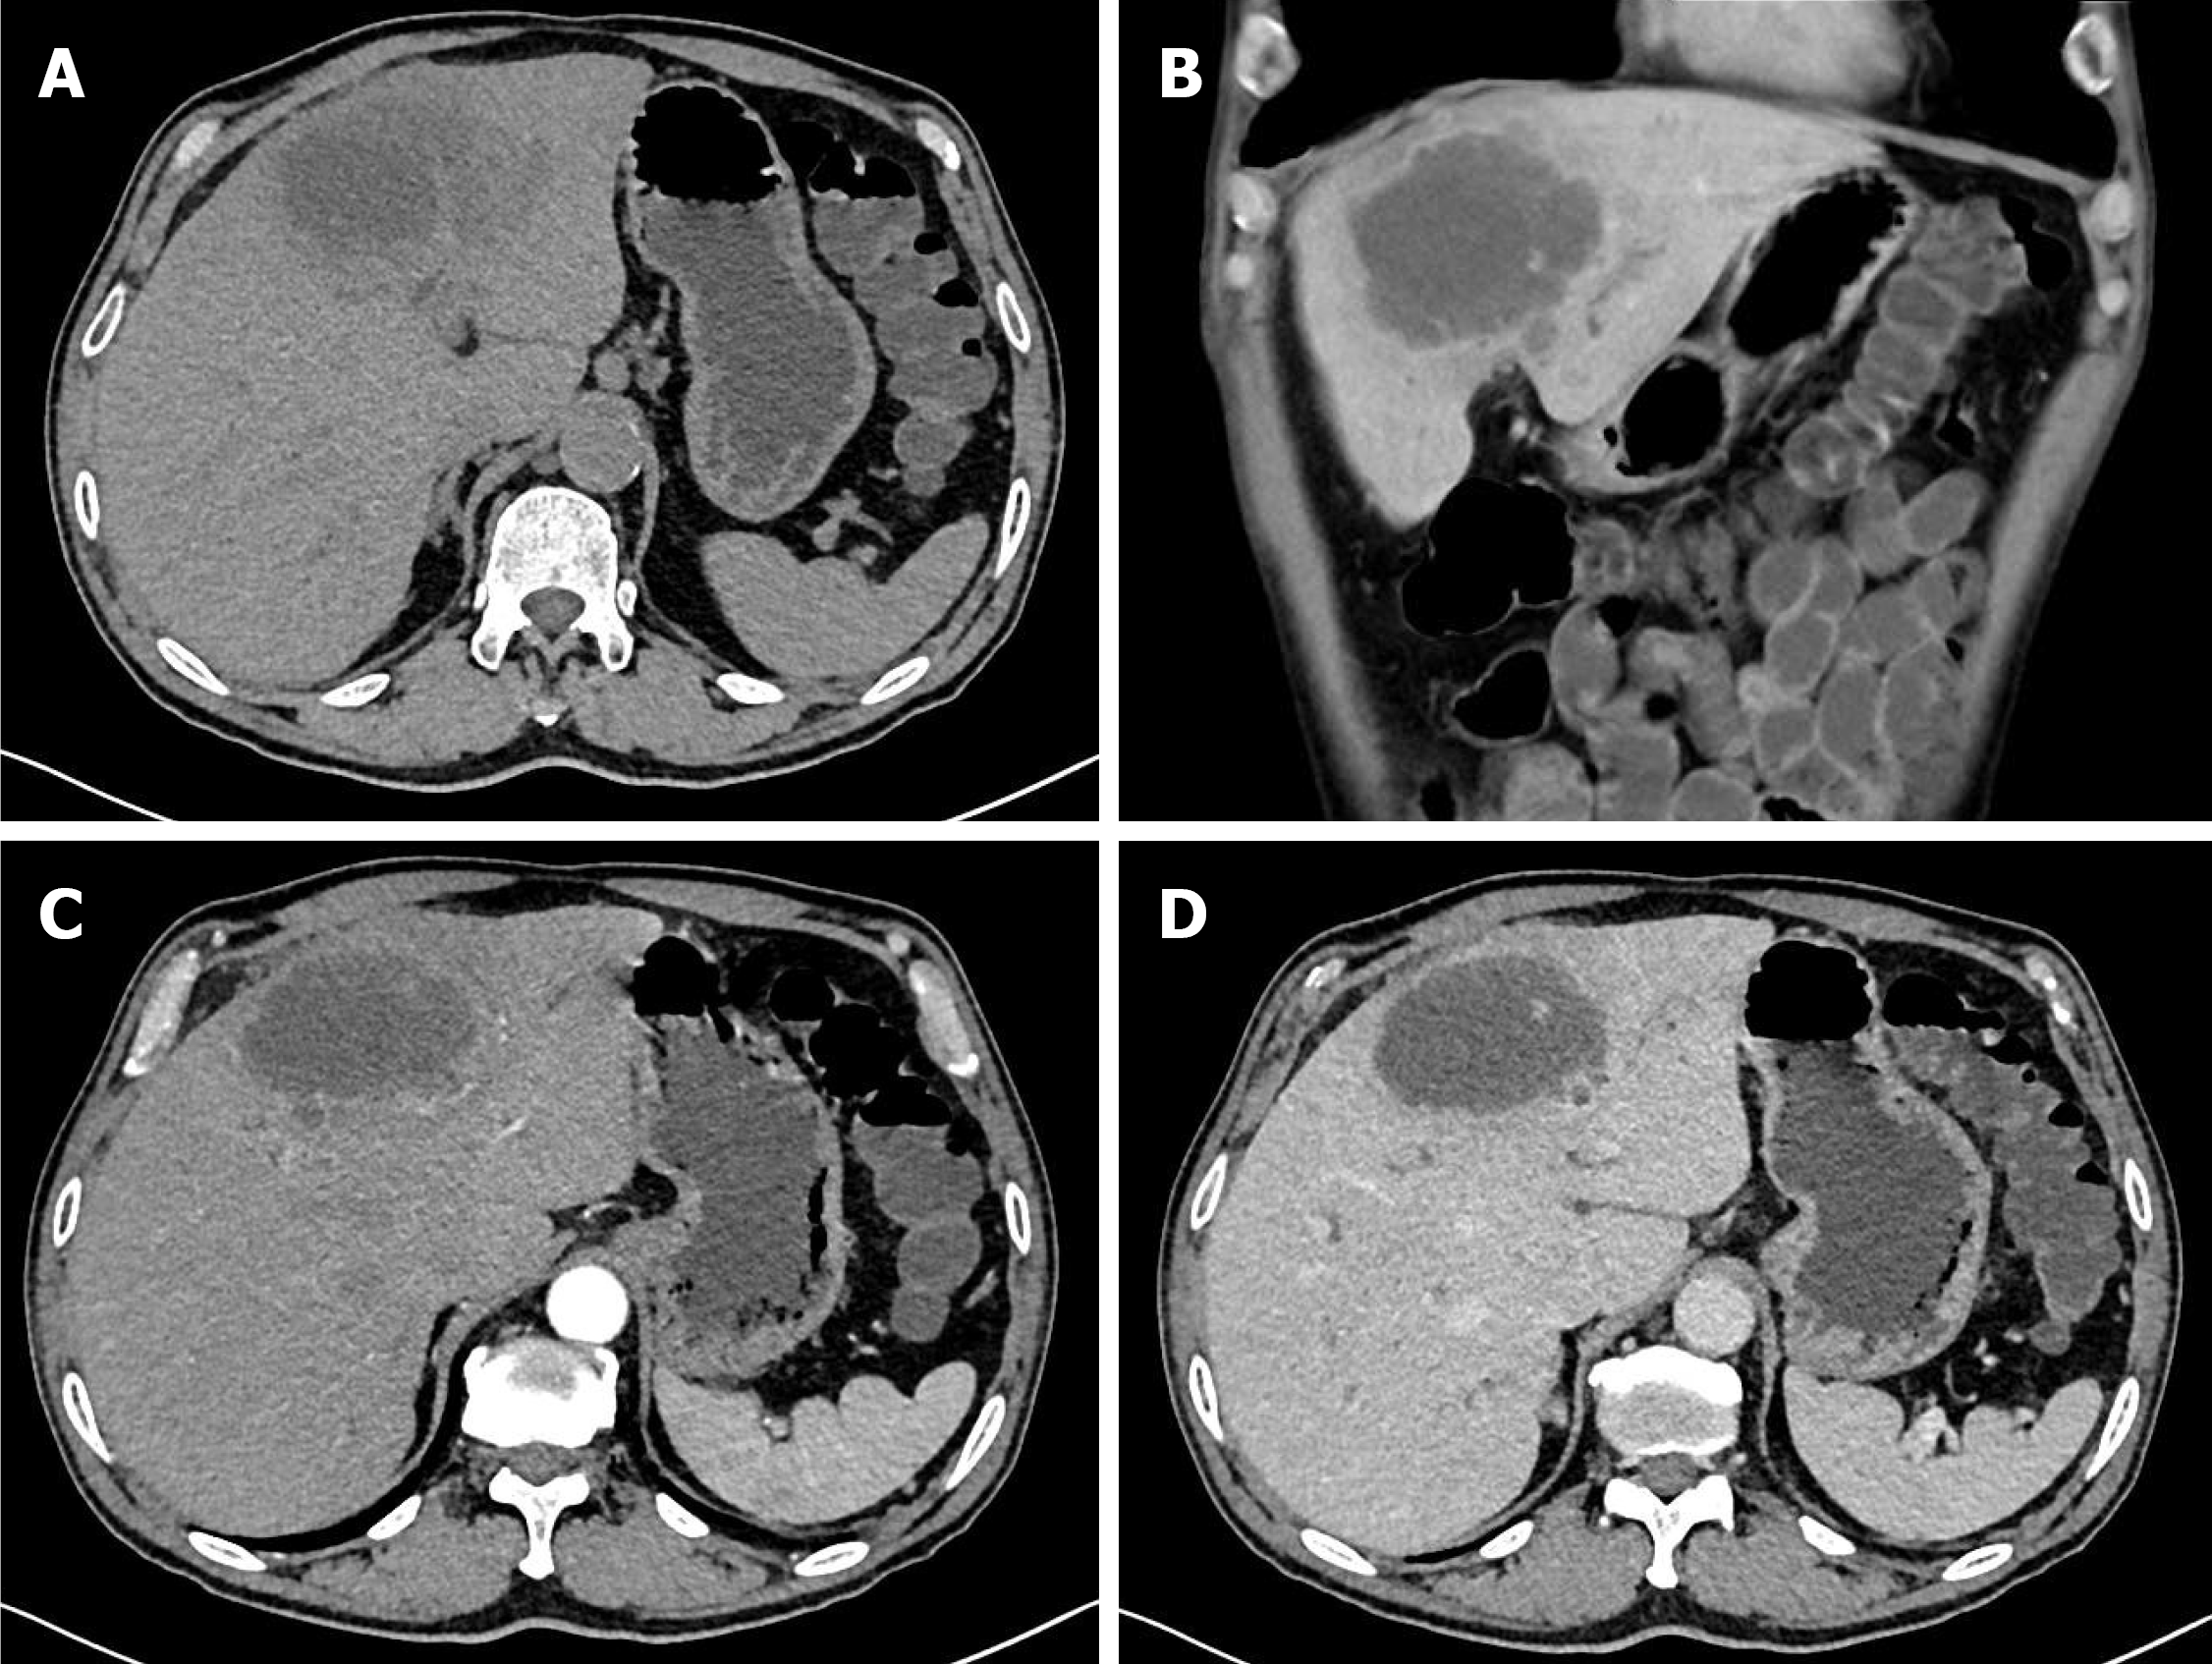

Figure 1 Computed tomography findings.

A and B: Abdominal computed tomography disclosed a low-density mass, 8 cm in diameter, with central necrosis in the left lobe of the liver; C: Enhanced abdominal computed tomography showed a peripheral irregular rim-enhanced mass in the left lobe of the liver without lymph node enlargement; D: Loss of enhancement of the peripheral irregular rim of the mass in the portal phase.